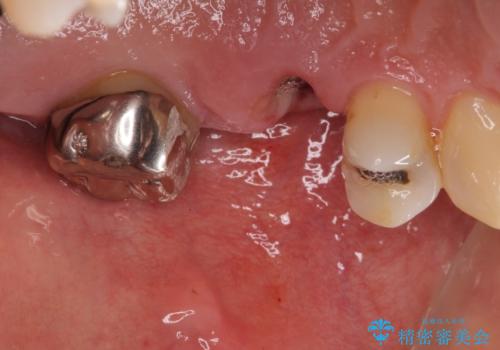

- 奥歯を他院で抜歯した後、インプラント治療を希望とのことで来院された患者様です。

ブリッジの支台を抜歯したことで2本のインプラントが必要であり、その後方はインプラント埋入に必要な骨量が不足していたため、上顎洞粘膜の挙上を行うこととしました。

また、残っている最後方歯は手前に倒れてきていたため、部分矯正により奥に移動させてから、インプラント埋入を行うこととしました。